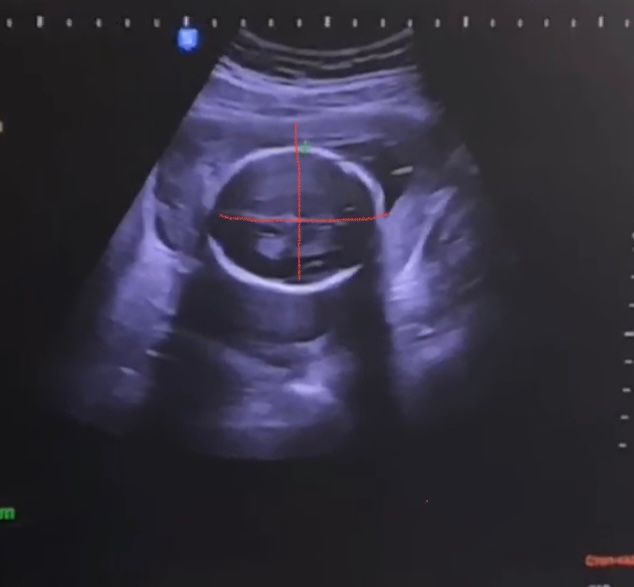

Душевные переживанияВсем привет! Вчера была на втором скрининге, узист сказала все хорошо, но придя домой обнаружила опечатку в БПР 68!

На видео наглядно видно что голова правильная, лзр 62 и это значение визуально больше бтр